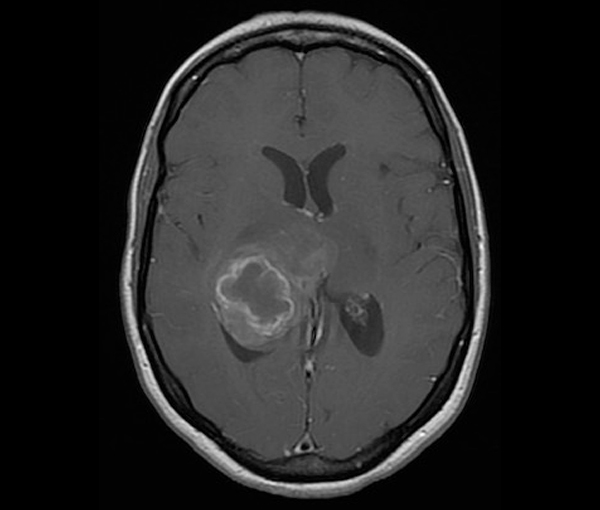

La caractérisation repose le plus souvent sur l’IRM dont les différentes modalités (imagerie morphologique, multiparamétrique et dynamique) permettent au radiologue dans certains cas de porter un diagnostic de certitude sur la nature d’une lésion tumorale (nodule hépatique, masse rénale…) en appliquant des classifications et des critères reconnus et très stricts qui permettent de s’affranchir d’une biopsie.

De plus, l’IRM est souvent utilisée pour l’évaluation précise du bilan d’extension locale (envahissement tumoral des structures anatomiques adjacentes à la tumeur) et pour l’évaluation du bilan d’extension régionale (atteinte des ganglions dans les premiers relais de drainage).

Certaines techniques d’IRM (Bili-IRM, Uro-IRM, IRM rectale avec opacification…) améliorent encore les capacités d’évaluation loco-régionale de la maladie, permettant ainsi une planification thérapeutique plus précise (chirurgie, radiothérapie…) pour améliorer le pronostic.

L’IRM dédiée à un organe (sein, rectum, foie…) permet, selon certains protocoles, d’évaluer la réponse loco-régionale après une première ligne de traitement (par exemple la réponse tumorale après une chimiothérapie néo-adjuvante dans le cancer du sein ou la réponse tumorale après une radio-chimiothérapie néo-adjuvante dans le cancer du moyen ou du bas rectum).